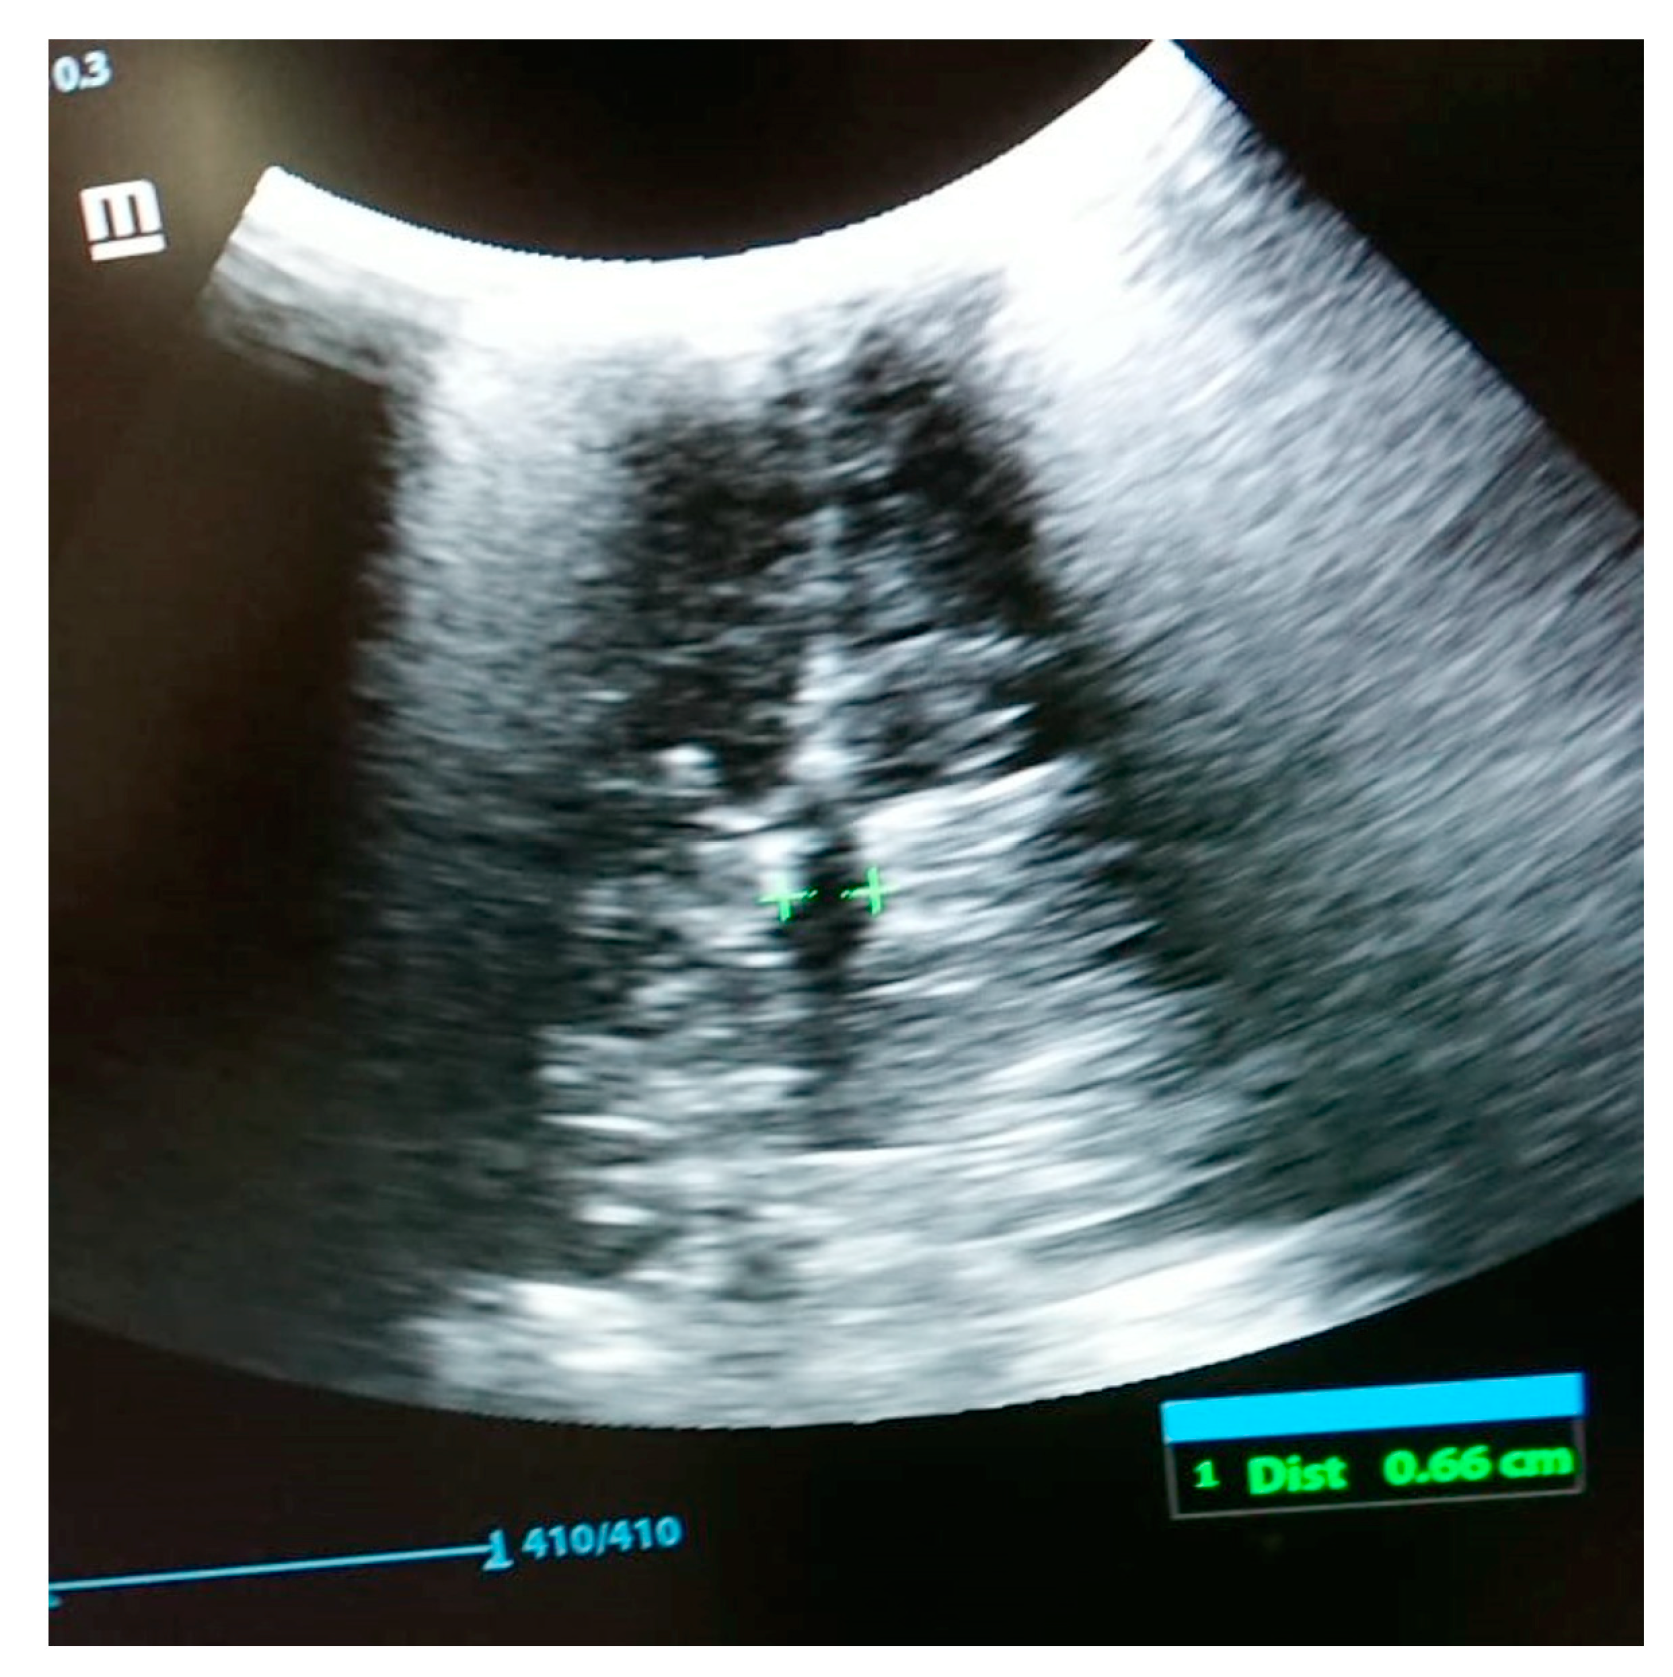

The following tests were carried out: brain ultrasound, skull X-ray, and head and neck CT scan. The brain ultrasound showed an enlargement of the third ventricle, and the corpus callosum was not detectable; since the examination was performed with an inappropriate probe (only the adult convex probe was available), it was not possible to visualize the cerebral cortex (Figure 3). On the skull X-ray, complete disorganization of the axillary and mandibular bones was revealed (Figure 4). To understand the malformation more precisely, a cranial CT scan was performed, which clarified the picture of bony disorganization of the maxillofacial complex; this examination revealed the presence of duplication of the mandible and, partially, the maxillary bones and the presence of a double opening of the oral cavity (Figure 5). Through CT image analysis of the central nervous system, it was possible to confirm the agenesis of the corpus callosum and the presence of a small anterior midline lipoma, a small posterior cranial fossa with the extension of the tonsils beyond the level of the foramen magnum was also found (Chiari I malformation) (Figure 6).

Figure 3. Brain ultrasound: enlargement of the third ventricle and agenesis of the corpus callosum.